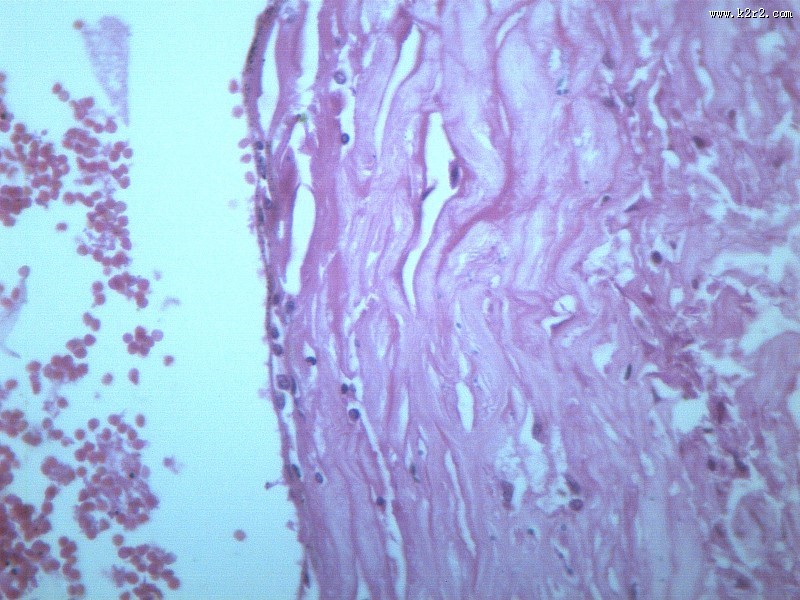

首页 > 其他类别 > 动脉粥样硬化(12张) > 动脉粥样硬化 第12张

动脉粥样硬化 - 第12张